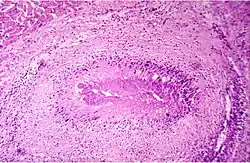

Die Gelenkzerstörung bei rheumatoider Arthritis ist vielmehr das Werk eines spezifischen onkologischen Prozesses, der sich schubweise aus der pluripotenten synovialen Zellmatrix entwickelt.[16][17] Die aggressiven homogenen Zellverbände, die in Knorpel und Knochen eindringen, bestehen aus dicht gelagerten großen polygonalen Zellen. Der große helle Zellkern enthält 1 bis 2 Nucleolen. Diese Zellen exprimieren eine Reihe hochpotenter proteolytischer Enzyme, die sie zur schnellen Zerstörung des Gelenks durch Degradierung von Knorpel und Knochen befähigen. Der gefäßfreie Prozess ist kurzlebig, die aggressiven Zellverbände kollabieren innerhalb weniger Tage und werden von Entzündungszellen und Makrophagen resorbiert. Entzündliche Faktoren sind am Zerstörungsprozess nicht beteiligt. Der Prozess hinterlässt jedoch den bekannten, oft fälschlich der Entzündung zugeschriebenen Pannus. Diese aggressive Phase kann sich am selben Gelenk wiederholen und den Zerstörungsprozess fortsetzen. Dieser für die rheumatoide Arthritis spezifische Prozess wurde vom Deutschen Krebsforschungszentrum als „tumor-like proliferation“ klassifiziert.

Eine weitere potenziell tödliche Komponente der rheumatoiden Arthritis ohne entzündliche Störung ist das akute Absterben von Geweben infolge einer lokalen Freisetzung von Kollagenasen. Es sind gelenkferne Prozesse, die durch eine zentrale Nekrose und eine dichte radiäre Zellpalisade gekennzeichnet sind. Sie zerstören gefäßarme, kollagene Strukturen. In Sehnen führen sie zur Sehnenruptur, im Auge befallen sie die Sklera, was zum Verlust des Auges führt. Sie können die Wandung von Arterien zerstören und damit zum Absterben von Gliedmaßen führen. Dies sind Prozesse, die sich der klinischen Beobachtung weitgehend entziehen und deswegen oftmals anderen Erkrankungen zugeschrieben werden (z. B. Herzinfarkt).[13]